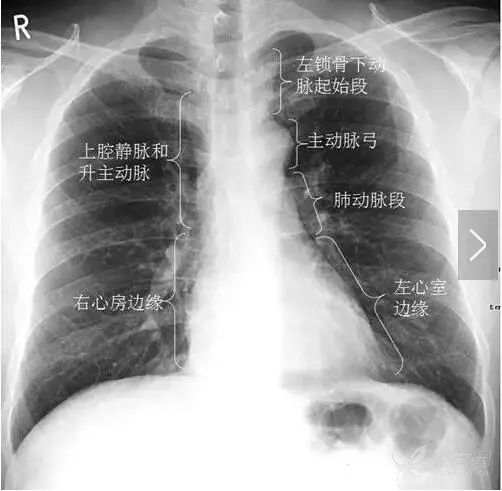

正位胸片上的纵隔 正常正位胸片上除心脏偏左外,基本处于居中的位置。右上纵隔边缘主要由上腔静脉构成,左上纵隔边缘主要是主动脉弓(也可称为主动脉球、主动脉结)和左锁骨下动脉起始段(图16)。中下纵隔边缘主要是心脏投影。

图16 正位胸片上纵隔正常边缘情况。